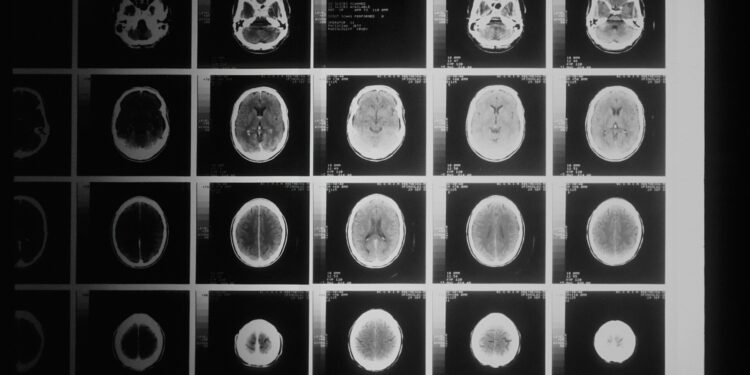

Συναγερμός στην ιατρική κοινότητα του Καναδά, για άγνωστη εγκεφαλική ασθένεια, που είχε προσβάλλει περισσότερους από 200 ανθρώπους.

Το 2021, οι υγειονομικές αρχές του New Brunswick προειδοποίησαν ότι περισσότεροι από 40 κάτοικοι έπασχαν από ένα πιθανό άγνωστο νευρολογικό σύνδρομο, με συμπτώματα παρόμοια με εκείνα της εκφυλιστικής εγκεφαλικής διαταραχής, που ονομάζεται Creutzfeldt–Jakob.

Τα συμπτώματα ήταν ποικίλα και κατά περιπτώσεις έντονα. Σε ορισμένους ασθενείς άρχισαν να τρέχουν σάλια και άλλοι ένιωθαν σαν να σέρνονται έντομα στο δέρμα τους. Ωστόσο, έναν χρόνο αργότερα, μία ανεξάρτητη επιτροπή εποπτείας που δημιουργήθηκε από την επαρχία διαπίστωσε ότι στην ομάδα των ασθενών πιθανότατα είχε δοθεί λανθασμένη διάγνωση.